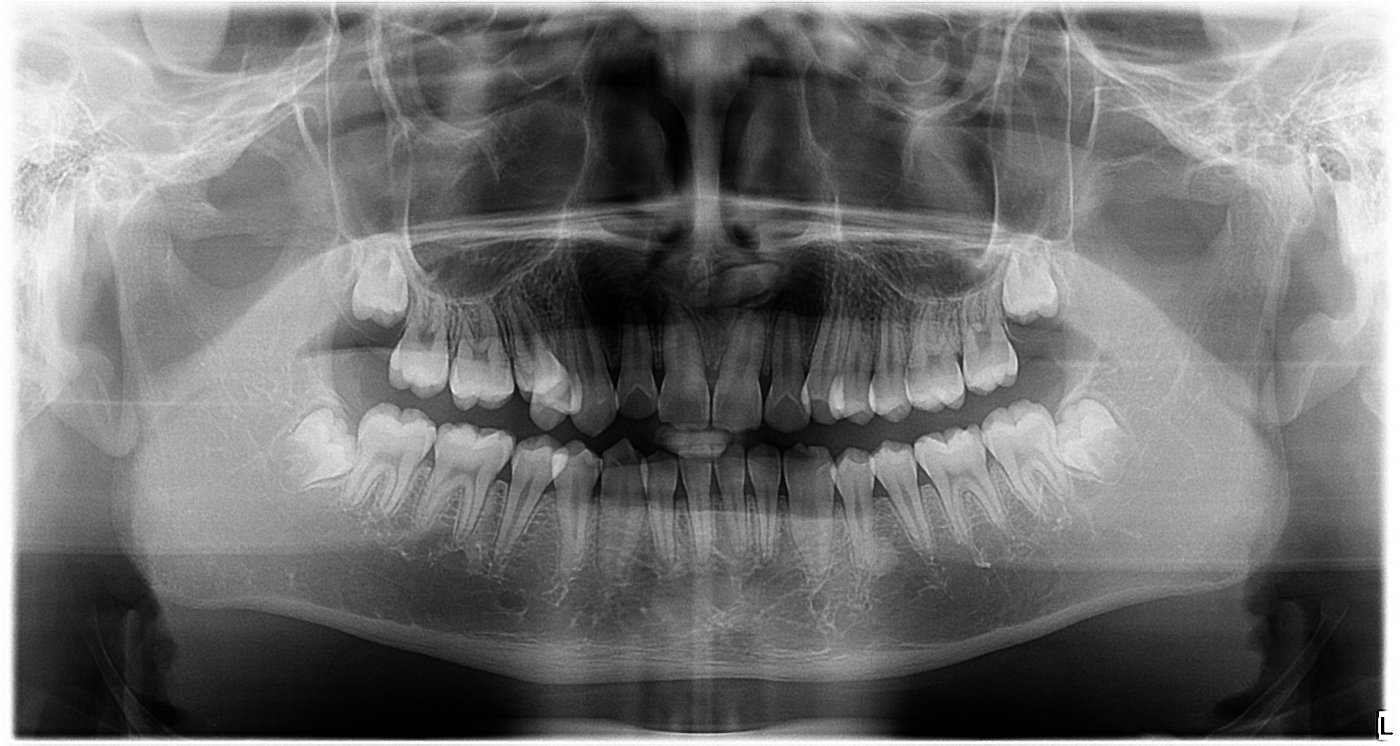

(1)拍摄两张x光片(包括全景片、侧位片)。

全景片